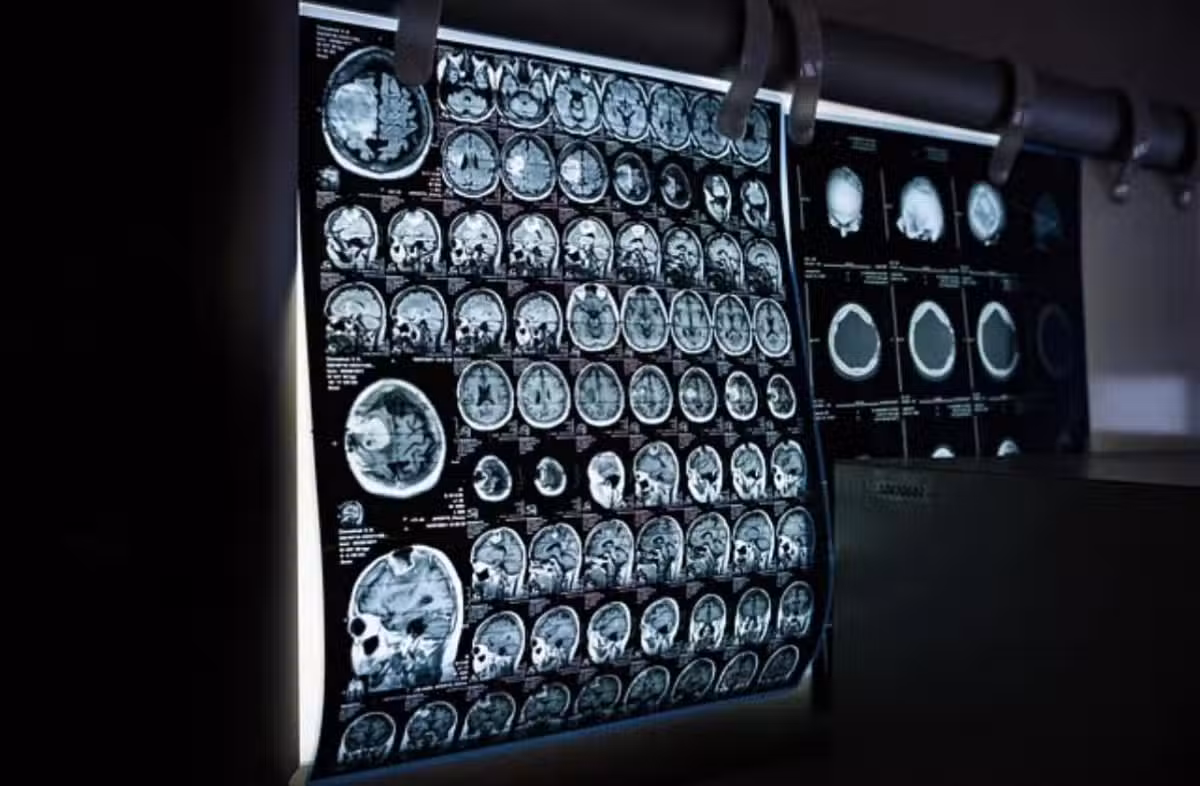

圖/翻攝自洪永祥醫師臉書

通常做電腦斷層或心導管、血管攝影等檢查,都需要靜脈注射顯影劑,注入體內後需要腎臟代謝,會造成血管收縮使得腎臟短暫的缺血性變化。通常腎功能正常的人不會有太大的影響,但慢性腎衰竭的患者則務必要小心,傷害會在注射後1~2天內出現,腎功能指數最高落在3~5天,通常1-2週內會自行恢復,但有部分四五期的患有,一次一次的注射導致急性腎損傷,尿毒症狀大爆發就開始洗腎。